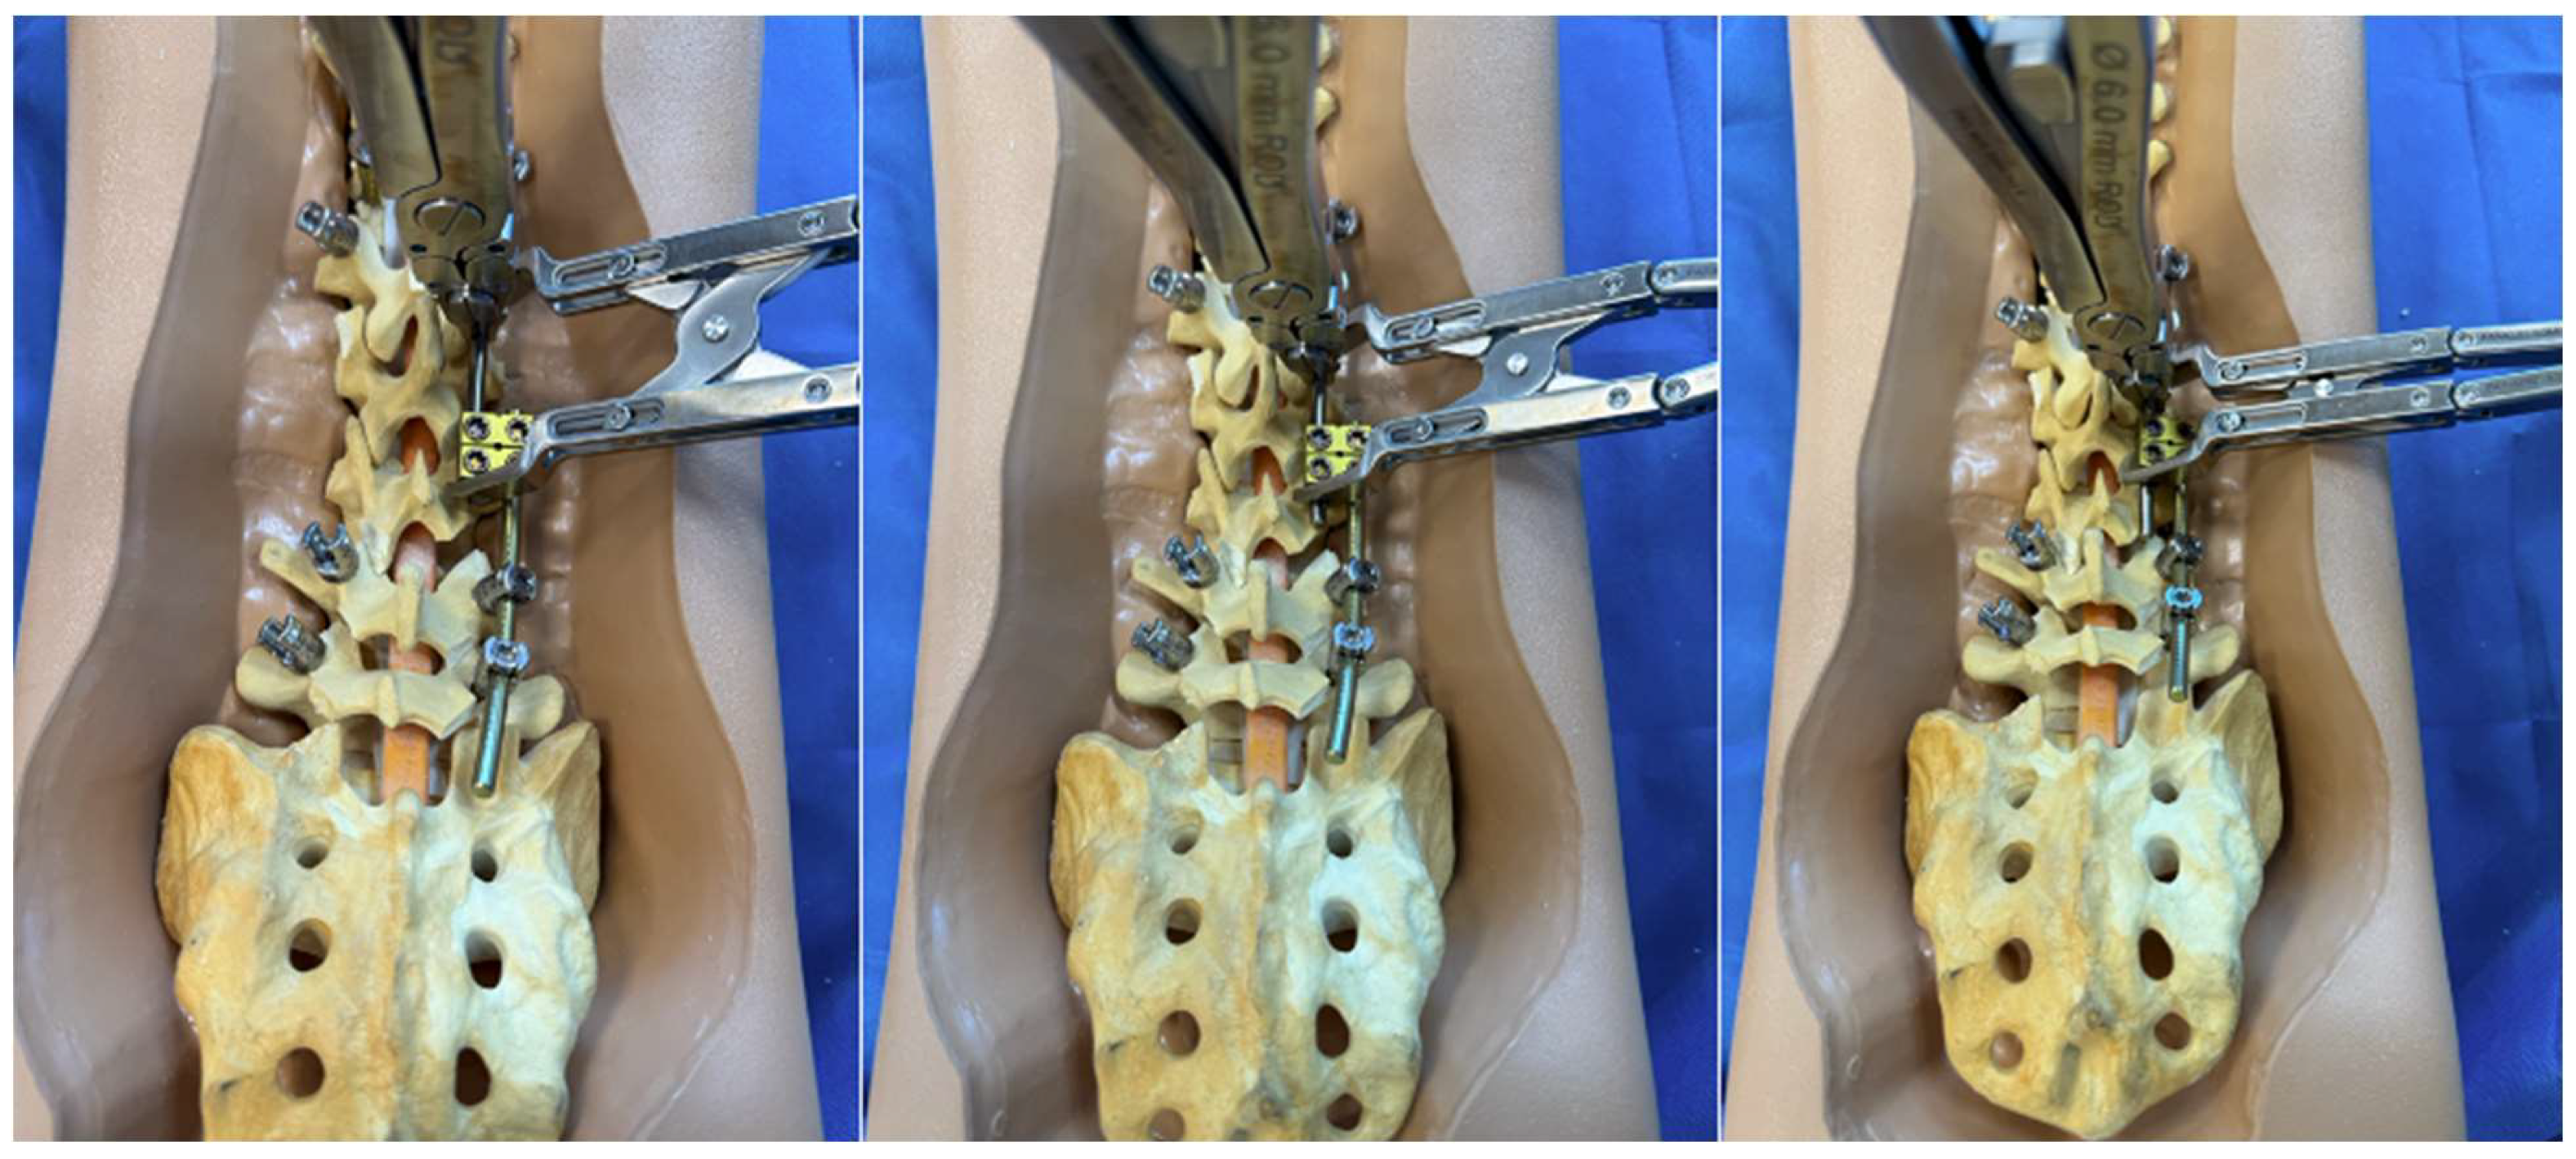

Figure 3.

Step-by-step schematic of the construct-to-construct internal distraction technique. The green caps represent loose set caps. Red caps represent tight set caps.

Figure 7.

Step-by-step schematic of the construct-to-construct internal compression technique for closure of PSO. The green caps represent loose set caps. Red caps represent tight set caps (A). Intraoperative image adapted from Bourghli et al. showing a construct-to-construct internal compression technique to close a PSO site (B).